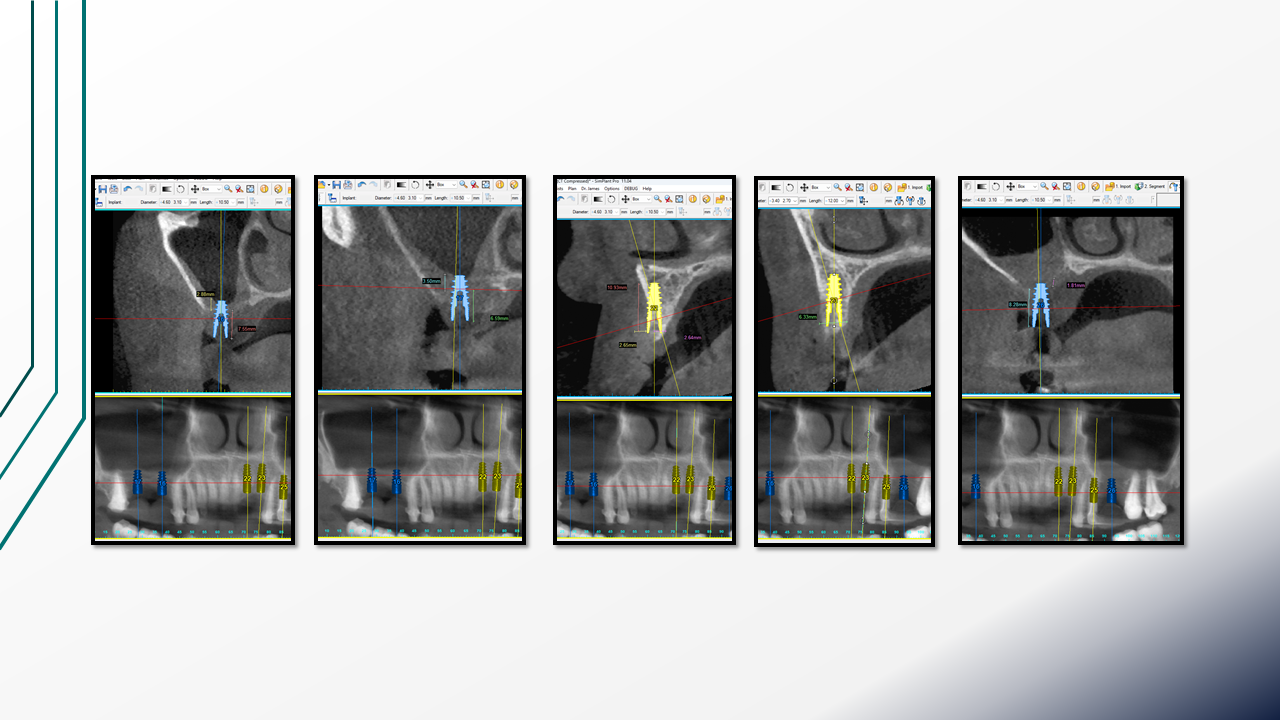

Titanium Mesh for Alveolar Ridge Reconstruction (16.03.2024 )

Clinical case of guided bone regeneration using a patient-specific 3D-printed titanium mesh in a pregnant patient. Multistage protocol with bone augmentation, implant placement, and soft tissue management. Presented by Dr. Levon Galstyan and Dr. Roza Hovhannisyan.